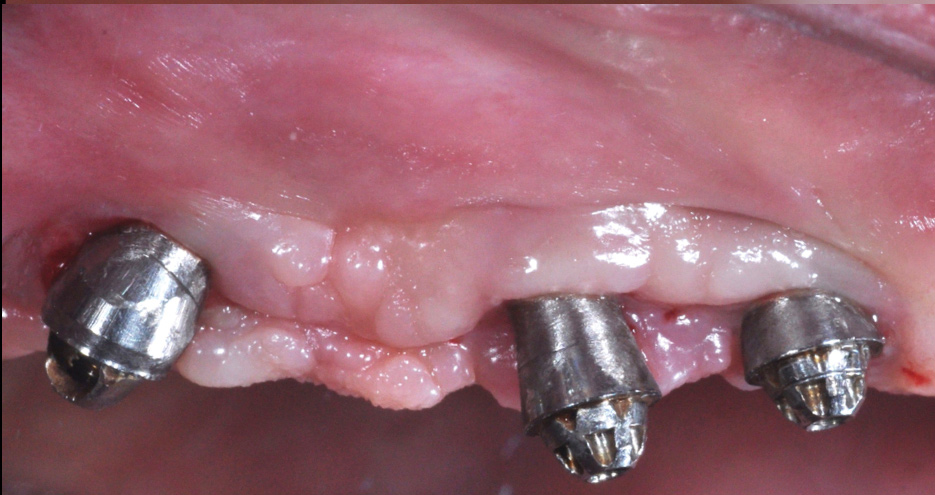

Following a similar paradigm of treating peri-implantitis the same way that periodontitis is regularly successfully treated, based on the mechanical removal of biofilms adhered to implant/abutment surfaces, different protocols of nonsurgical implant debridement using different mechanical, physical, and chemical mechanisms have been evaluated (Figure 12 through Figure 15). In general, the use of different protocols combining treatments aimed to decontaminate the implant surface (eg, mechanical, lasers) and control the infection process (eg, antiseptics, antibiotics) have shown clinical and significant improvements in the commonly used surrogate outcomes (mean reductions in PPD of around 1.2 mm and mean reductions in the scores of BOP of about 50%) but have not resulted in disease resolution18 or a high degree of predictablility.19 There is currently no specific nonsurgical therapy that has shown efficacy in the resolution of peri-implantitis, and the clinical improvements reported in the clinical studies were not sufficient for the arrest of the disease, leaving the standard of care in the treatment of peri-implantitis as surgical in most cases.20

One controversial aspect in the treatment of peri-implantitis is whether implant surface roughness may play a relevant role in the progression of the disease and treatment efficacy, since when exposed to the oral cavity, rough surfaces have been shown to accumulate more plaque than smooth surfaces.25 Some authors have proposed smoothing and polishing the exposed rough implant surface during surgical treatment of peri-implantitis (implantoplasty), not only with the goal of removing surface contamination, but also to reduce future bacterial colonization (Figure 16 through Figure 19). A clinical trial comparing implantoplasty with standard access surgery demonstrated significantly improved clinical outcomes and maintenance of peri-implant bone levels over a 3-year period.26 There is, however, controversy on whether this implant surface elimination would structurally damage the implant or contaminate the surrounding tissues. Recent in vitro studies have confirmed that implantoplasty, although technically demanding and time-consuming, does not seem to significantly alter fracture resistance of standard-diameter external connection implants.27

Fig 12. Treatment of peri-implantitis: peri-implant mucosal inflammation associated with plaque and calculus accumulation.

Figure 12

Fig 14. After removing the prosthesis, presence of peri-implant plaque and calculus.

Figure 14

Fig 15. Access flaps to allow mechanical debridement of implant surfaces.

Figure 15

Fig 16. Treatment of peri-implantitis: access flap with exposed implant surfaces after being decontaminated.

Figure 16

Fig 17. Implantoplasty of exposed implant surfaces.

FIgure 17

Fig 18. 1-year postoperative view.

Figure 18

Fig 19. 3-year postoperative view.

Figure 19